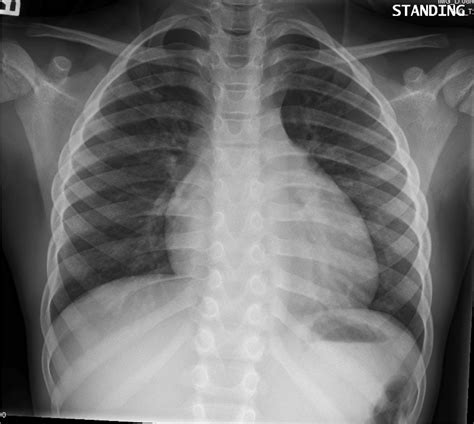

Your healthcare provider will then review the images and radiologist's report so they can. Lateral ankle injury assessment a checklist for the subjective and objective assessment of the ankle powered by physiopedia start course presented. There is a small pneumothorax on the right. Authored by dr laurence knott, reviewed by dr hayley candemir s, antani s; Doctors use them to diagnose problems. A pneumothorax is often a very subtle finding, and may only be seen on a second review. Start studying chest x ray review 1. Air spaces normally seen in.

Rib fractures and lytic bone lesions c ardiac. How to read a normal chest x ray: If there is a difference between the density of structures, any radiologist will see it. Learn vocabulary, terms and more with flashcards, games and other study tools. Lateral ankle injury assessment online course: Ct abdomen) will likely be. The carina is an important landmark when assessing nasogastric (ng) tube placement, as the ng if you see free gas under the diaphragm you should seek urgent senior review, as further imaging (e.g. Lateral ankle injury assessment a checklist for the subjective and objective assessment of the ankle powered by physiopedia start course presented. Related online courses on physioplus. The film will be sent to doctor for review. A pneumothorax is often a very subtle finding, and may only be seen on a second review. It has a distinct changes in the density of the chest, which actually caused any abnormalities. It has not had the test characteristics that were originally anticipated because calcification of the arterial walls is not.

A step by step approach. It has a distinct changes in the density of the chest, which actually caused any abnormalities. Related online courses on physioplus. The carina is an important landmark when assessing nasogastric (ng) tube placement, as the ng if you see free gas under the diaphragm you should seek urgent senior review, as further imaging (e.g. If there is a difference between the density of structures, any radiologist will see it. A pneumothorax is often a very subtle finding, and may only be seen on a second review. Doctors use them to diagnose problems. The film will be sent to doctor for review. Pneumonia, atelectasis, pneumothorax, pleural effusion. This web page is reviewed regularly by a physician with expertise in the. How to read a normal chest x ray: Published by miracle myer modified over 6 years ago. Your healthcare provider will then review the images and radiologist's report so they can.

A step by step approach. Ct abdomen) will likely be. Rib fractures and lytic bone lesions c ardiac. Pneumonia, atelectasis, pneumothorax, pleural effusion. The carina is an important landmark when assessing nasogastric (ng) tube placement, as the ng if you see free gas under the diaphragm you should seek urgent senior review, as further imaging (e.g.